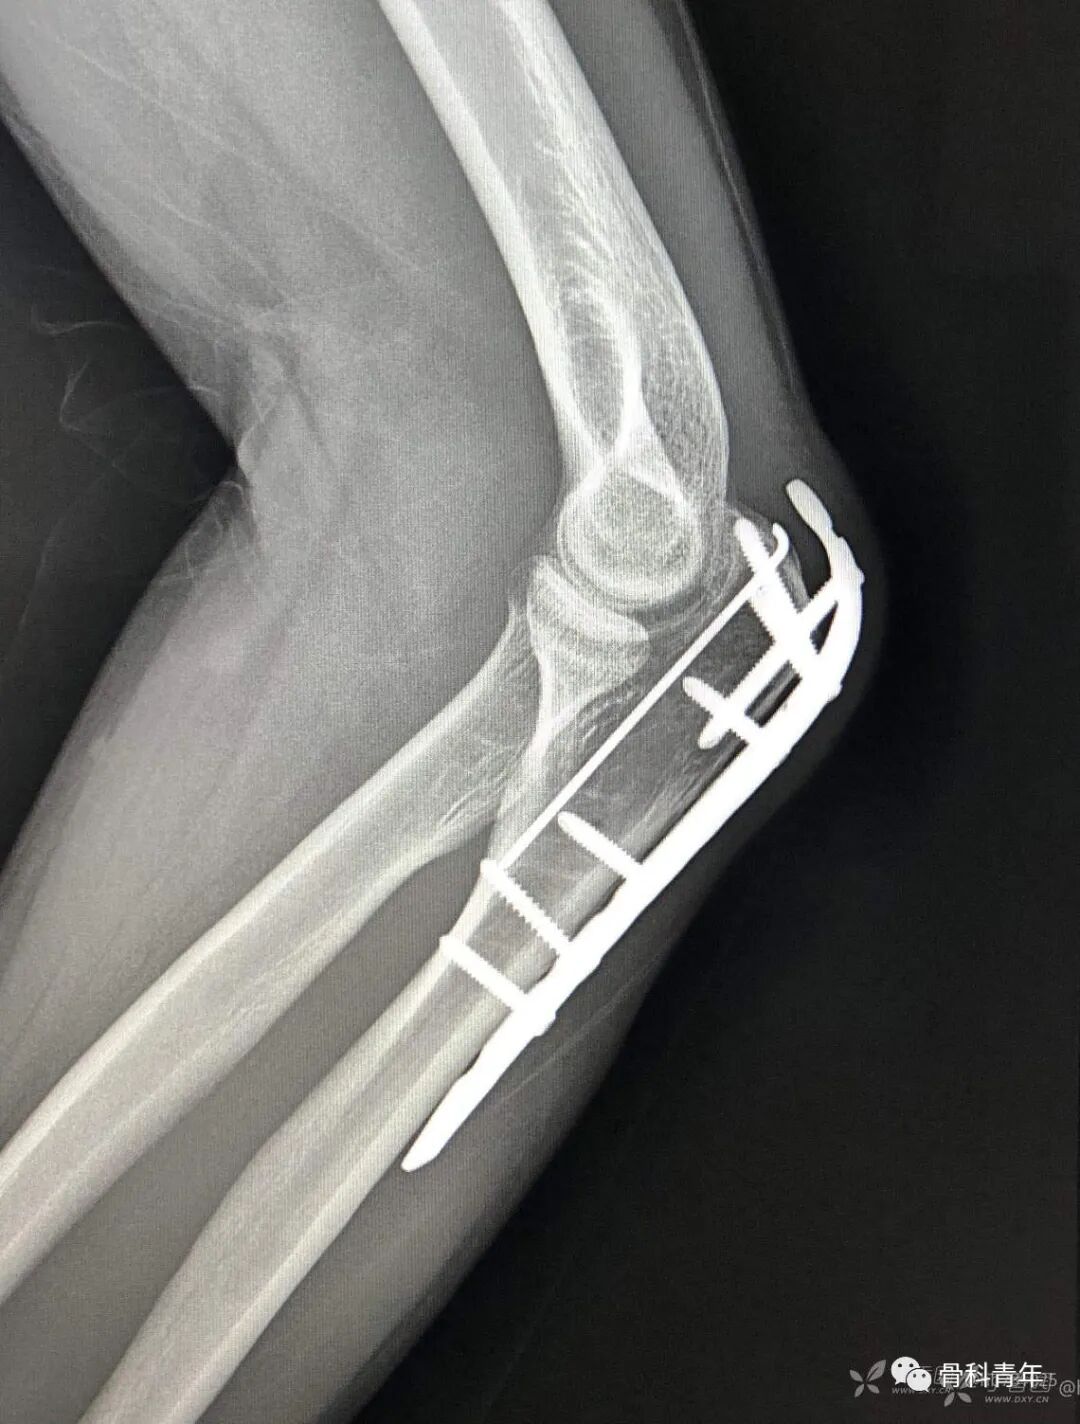

23.尺骨鹰嘴骨折